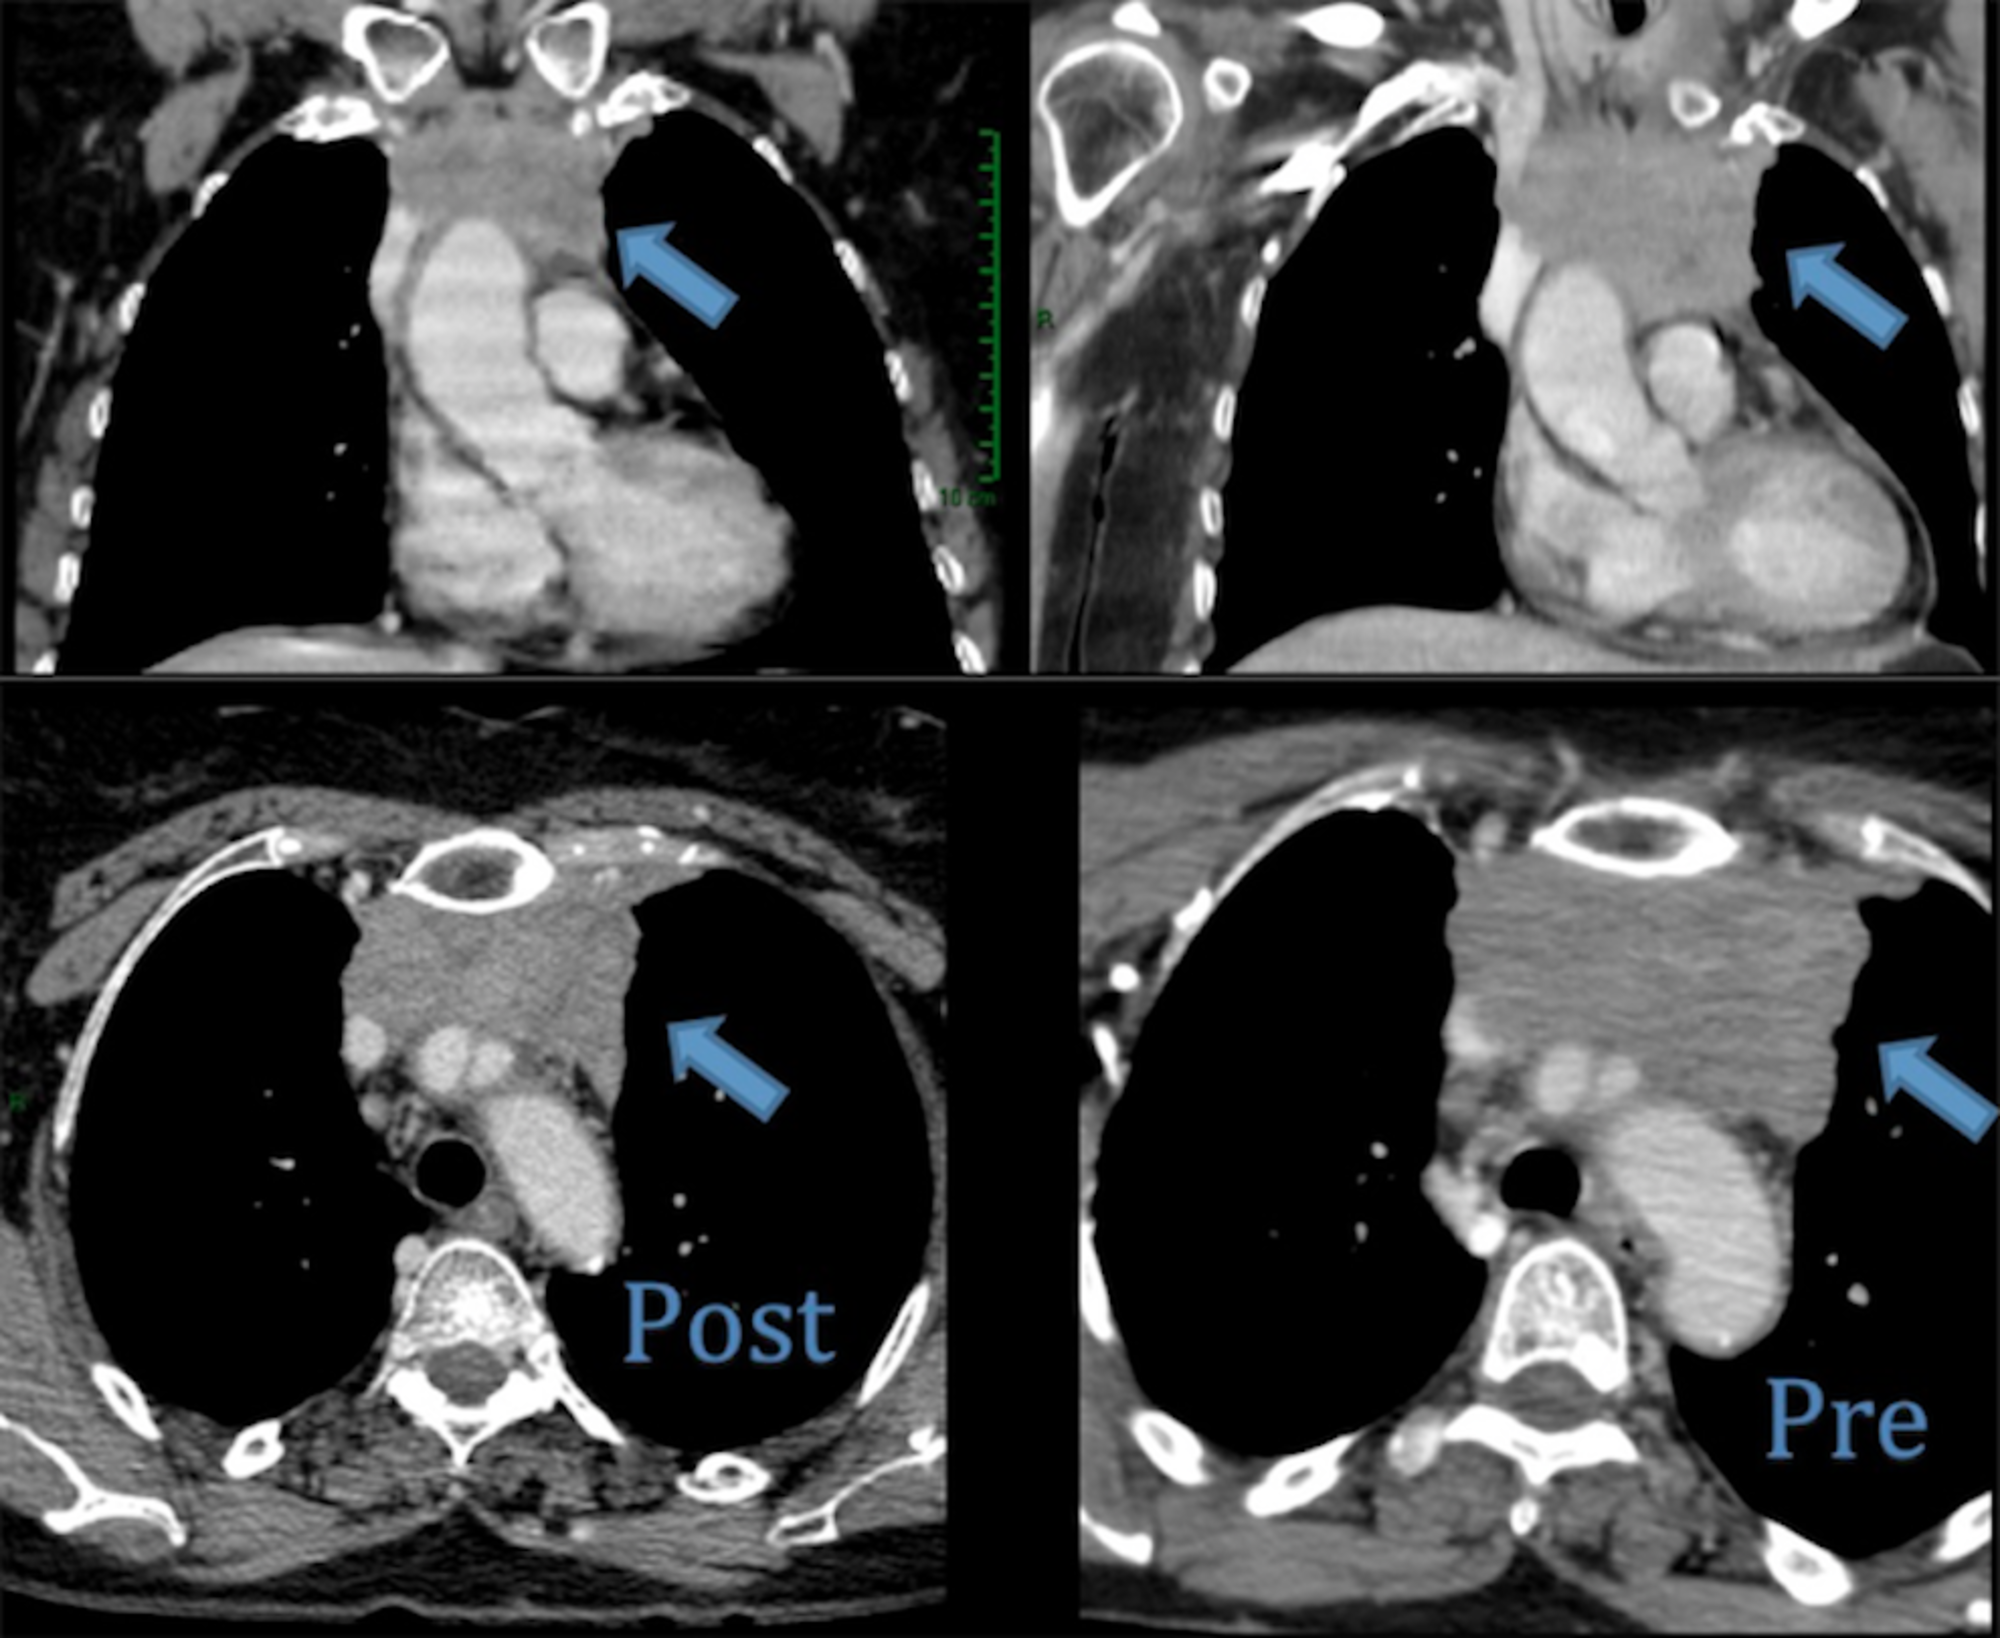

Image series of metastatic thymic carcinoma. a Coronal PET CT showing Thymic Metastasis Thymic carcinoma (tc) is a rare thymic epithelial neoplasm (ten) with heterogeneous features. As thymomas grow, they spread (metastasize) to nearby tissues and can travel to organs throughout the body. Thymic epithelial tumors hold a unique place. The latest world health organization (who) classification from 2015 has grouped lung and thymic neuroendocrine tumours (nets) (named neoplasm in the digestive who. Thymic Metastasis.